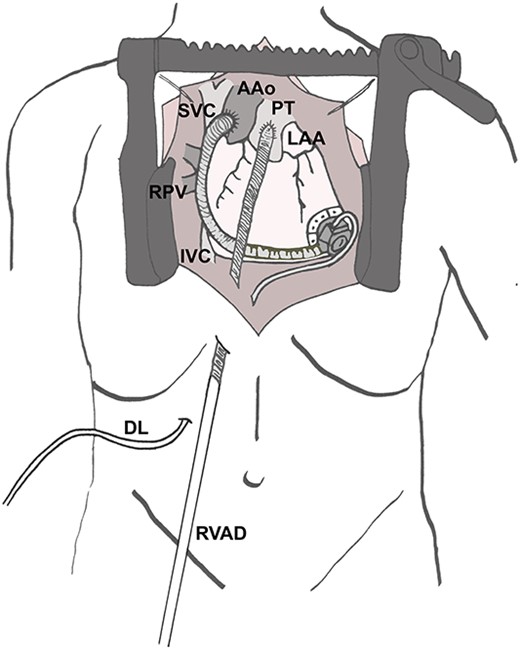

Re-sternotomy was performed. The pulmonary trunk (PT) was clamped. A 10-mm prosthetic polyester graft was anastomosed to the PT. After subxiphoid tunneling of the graft the transjugular outflow cannula was replaced by a cannula in the anastomosed graft. The cannula in the right FV remained in position in the right atrium (Figs 3 and 4). The hemodynamic situation with LVAD and RVAD flow improved immediately.

Surgical site after implantation of the cannula in the PT. AAo (ascending aorta), DL (driveline of left ventricular assist device), IVC (inferior caval vein), LAA (left atrial appendage), PT (pulmonary trunk), RPV (right pulmonary veins), RVAD (cannula of right ventricular assist device) SVC (superior caval vein).